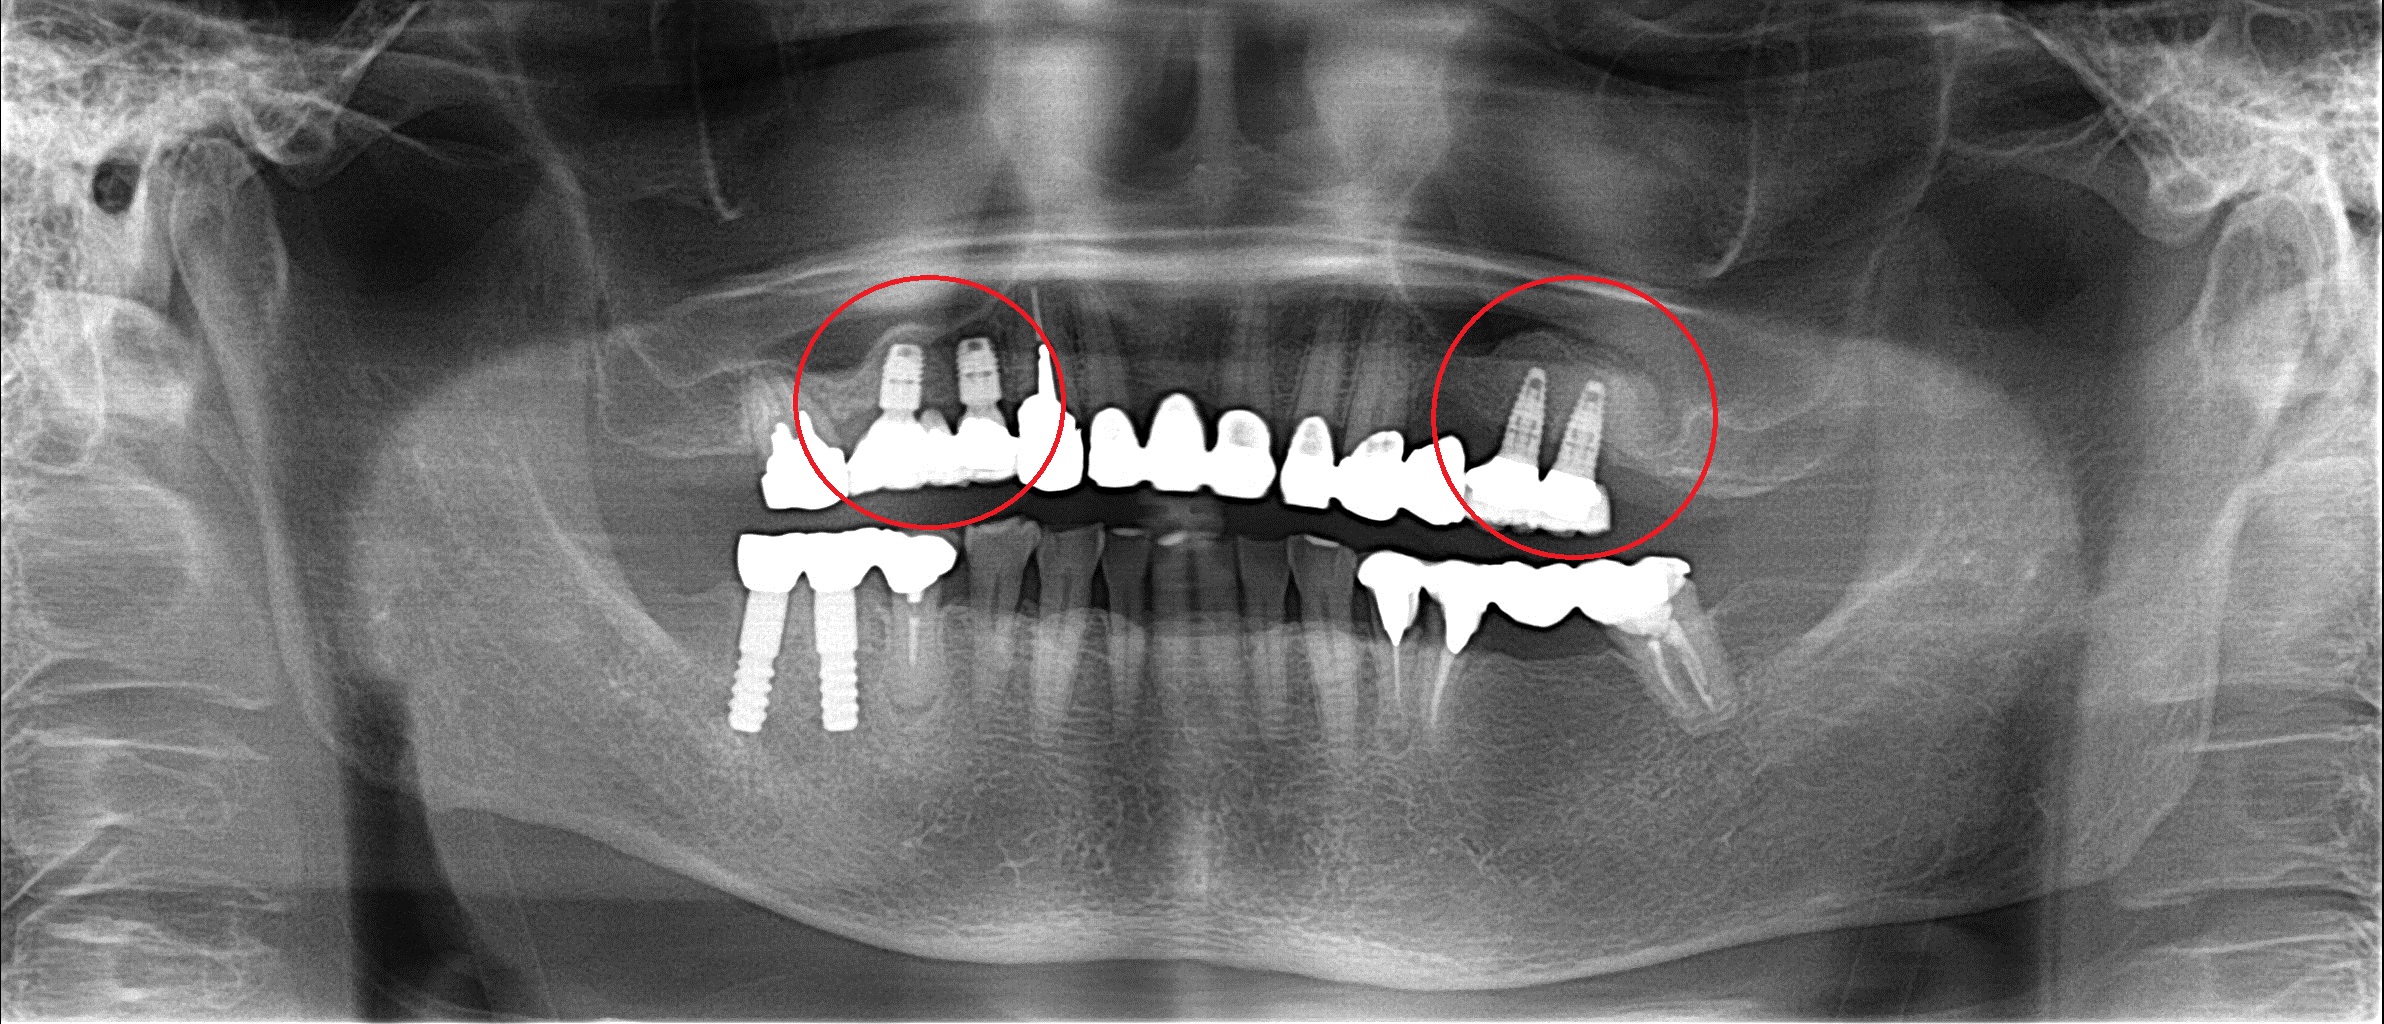

初めて来院した時のレントゲン ↓

黄色の丸の部分は他院でのインプラント治療です。

そこの歯医者さんでは上の顎には下の顎のように

骨がないのでインプラントはできない!と言われ

長い間、入れ歯を装着していたそうです。

確かに赤い丸の部分には骨の高さが少し足りないですが

全く問題なくインプラントできるケースです。